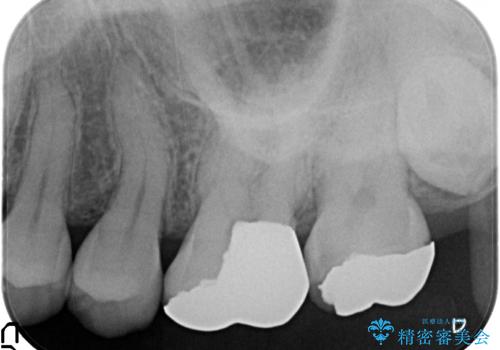

- 舌で触ると段差が大きく気になる銀歯の改善を求めて来院されました。

複雑な形態の銀歯の下には虫歯が再発しており、虫歯を丁寧に除去したのちジルコニアクラウンによる機能回復を行います。